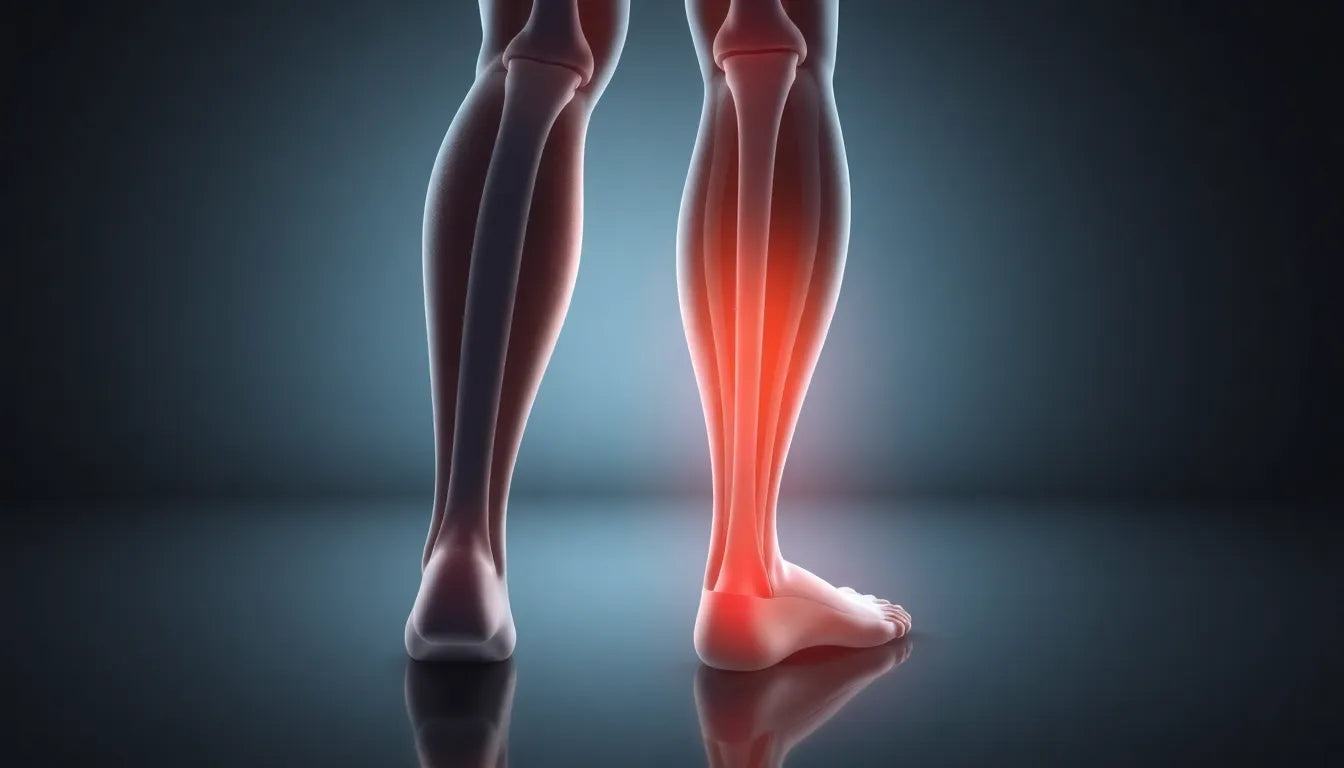

Het is niet ongebruikelijk dat pijn in de bovenbuik naar de rug uitstraalt. Dit komt doordat de zenuwen in de buik en rug nauw met elkaar verbonden zijn. Aandoeningen zoals galstenen en pancreatitis kunnen bijvoorbeeld pijn veroorzaken die voelbaar is in zowel de buik als de rug. Dit fenomeen kan het moeilijk maken om de exacte bron van de pijn te lokaliseren.

Het begrijpen van de relatie tussen buik- en rugpijn is essentieel voor het vinden van effectieve oplossingen. Of de pijn nu voortkomt uit een medische aandoening of een houdingsprobleem, het is belangrijk om de juiste stappen te ondernemen voor diagnose en behandeling.